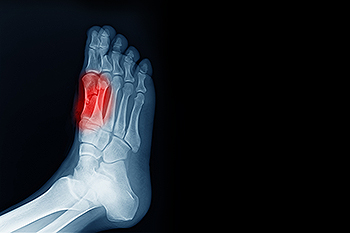

Bunion Treatment

Bunions are a common foot deformity where the joint at the base of the big toe becomes enlarged and misaligned, causing the toe to angle inward. This can lead to pain, swelling, and difficulty in finding comfortable shoes. The condition often develops due to genetic factors, wearing ill-fitting footwear, or arthritis. If you have bunions, it is essential to take proactive steps to manage the discomfort and prevent further progression. Start by wearing shoes with a wide-toe box, low heels, and good arch support. Regularly performing foot exercises to strengthen the muscles around the joint can also provide relief. If these conservative measures do not help, or if the bunion becomes severely painful, it is suggested that you consult a podiatrist. In some cases, surgery may be recommended to correct the deformity and restore foot function.

What Is a Bunion?

Bunions are painful bony bumps that usually develop on the inside of the foot at the joint of the big toe. As the deformity increases over time, it may become painful to walk and wear shoes. Women are more likely to exacerbate existing bunions since they often wear tight, narrow shoes that shift their toes together. Bunion pain can be relieved by wearing wider shoes with enough room for the toes.

Causes

- Genetics – some people inherit feet that are more prone to bunion development

- Inflammatory Conditions - rheumatoid arthritis and polio may cause bunion development

Symptoms

- Redness and inflammation

- Pain and tenderness

- Callus or corns on the bump

- Restricted motion in the big toe

In order to diagnose your bunion, your podiatrist may ask about your medical history, symptoms, and general health. Your doctor might also order an x-ray to take a closer look at your feet. Nonsurgical treatment options include orthotics, padding, icing, changes in footwear, and medication. If nonsurgical treatments don’t alleviate your bunion pain, surgery may be necessary.